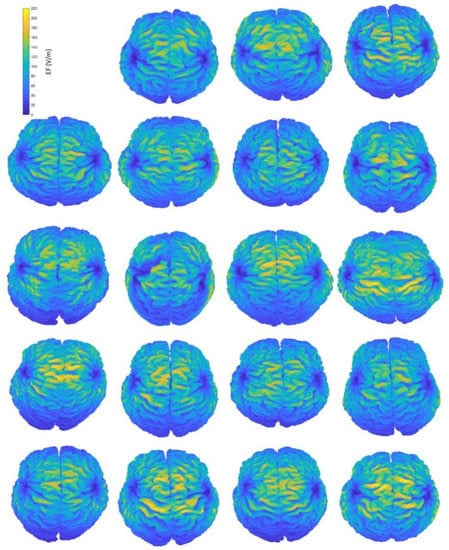

Figure 2.

Interindividual variability of the induced EF distributions visualized in subject brains, containing both grey and white matter, when the H-coil is placed at the central position. Head and brain anatomy affect the area and magnitude of stimulation. Brain coordinates are plotted on their natural space.

Figure 2 provides an indicative visual description of the variations in TMS-induced EFs for anatomical models and central coil positioning. Corresponding figures for homogeneous models and frontal coil positioning can be found in Appendix A. Complementary to EF visualization, Figure 3 and Figure 4 show the EF distributions in individual brains as violin plots and IQRs, providing a comparison across models and between their anatomical and homogeneous versions, for the two coil positions.

A simple visualization of the computed EF on the brain suffices to show the interindividual differences of the induced distributions, resulting from anatomical variations (Figure 2). Natural space coordinates were selected to highlight the morphology diversity that clinicians encounter during a TMS session. The distinctive characteristics of participants, such as the shape and size of their head, or even the head pose during the TMS session, have the potential to change the coil fitting and alter the stimulation’s outcome, influencing both the stimulated area and the magnitude of stimulation. This study focuses on parameters that can be measured and attempts to associate the stimulation characteristics with four of them, including age and total volumes of head, CSF (excluding the ventricles) and brain. Furthermore, homogeneous models are not affected by the electrical conductivity distribution, which is present only in anatomical models, carrying the information of tissue distribution. Therefore, the variation of the EF in homogeneous models reflects mainly the effects of head shape and size, whereas the variation of the EF in anatomical models incorporates the effect of individual tissue anatomy.